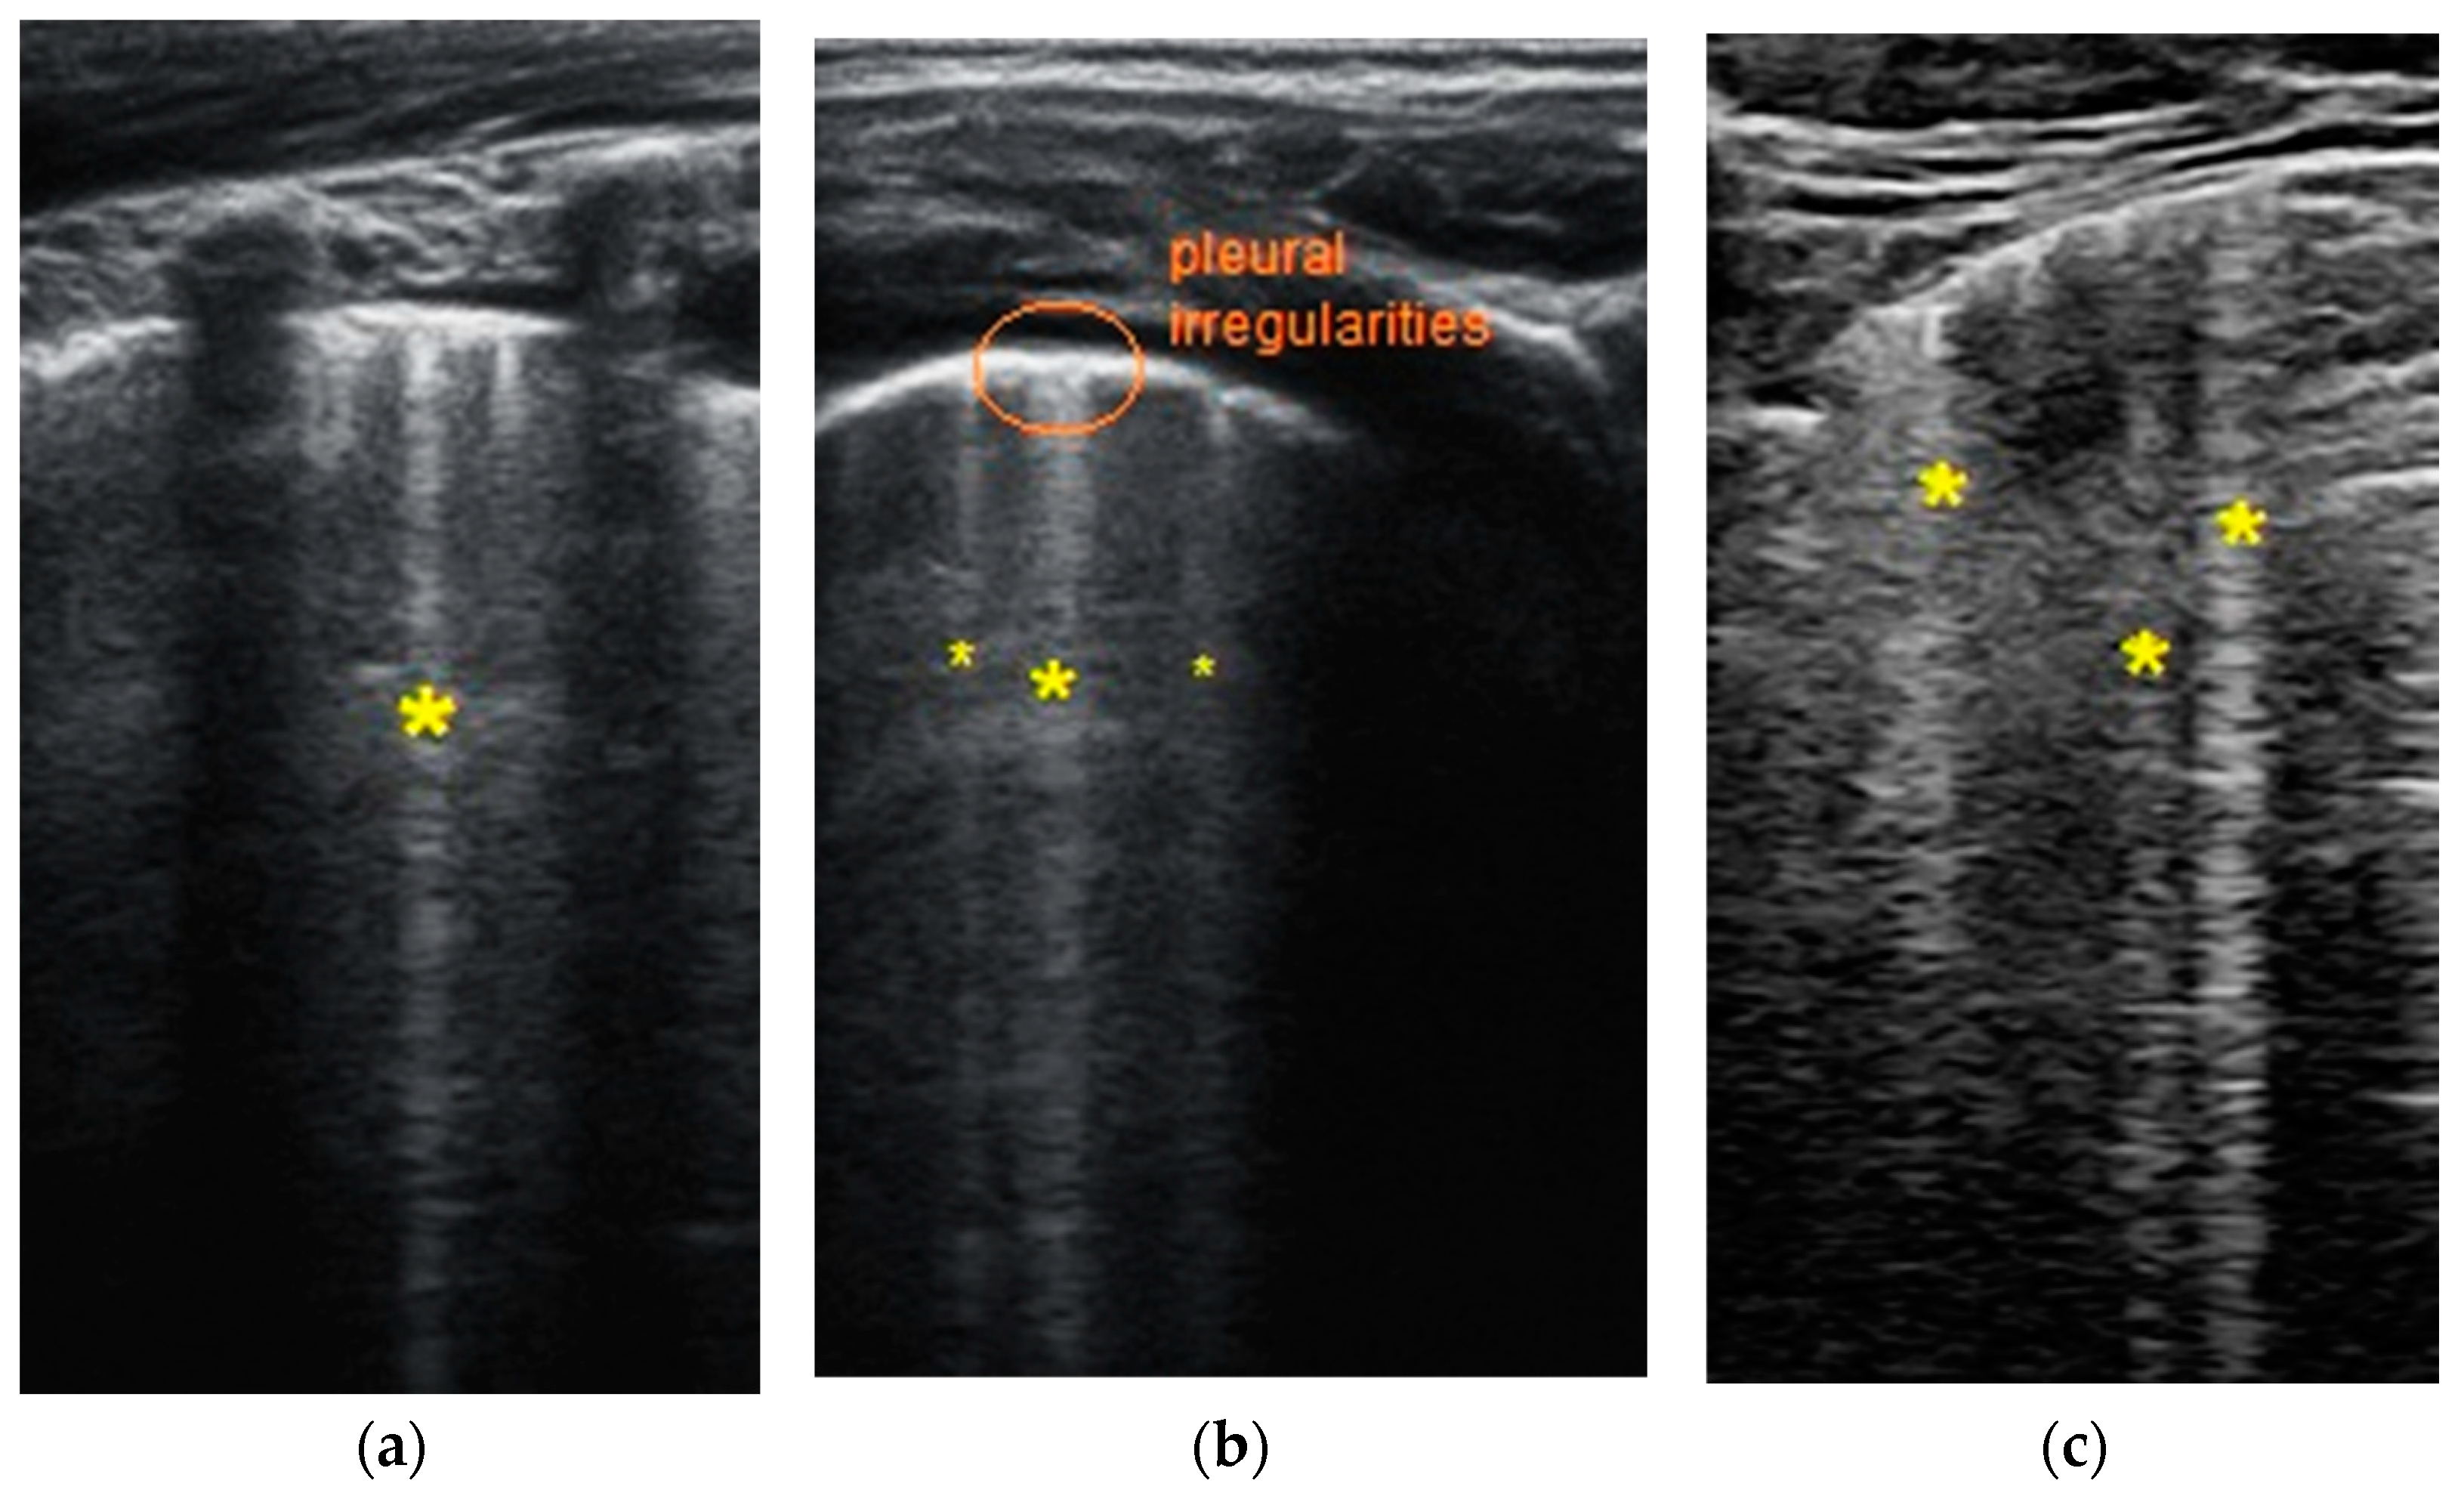

- Transverse physiologic A-lines that depict healthy parenchyma;

- Isolated/sparse vertical B-lines are equivalent to interstitial edema;

- Confluent vertical B-lines correspond to alveolar edema;

- Subpleural/peripheral consolidations;

| LUSS = 0 Points | LUSS = 1 Point | LUSS = 2 Points | LUSS = 3 Points |

|---|---|---|---|

| Normal/physiological A-lines | More than 2 B-lines (sparse B-lines) with associated pleural abnormalities | Coalescent or confluent B-lines | Large peripheral consolidation (wider than 1 cm) in association or not with air bronchogram |

| One or two B-lines per intercostal space | ‘White-lung’ aspect or small peripheral consolidation (smaller than 1 cm) |